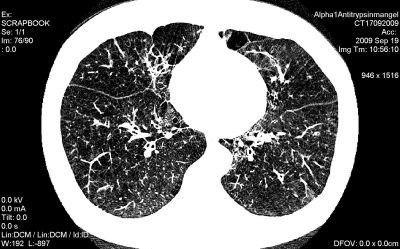

الفا۔ون کئی بچوں میں پیدائشی طور پر جگر کے مخصوص حصوں میں پائی جاتی ہے جو دیگر مادہ یا خلیات کے حفاظتی میکانزم کے خلاف کام کرتے ہیں الفا ۔ون کو پھیپھڑوں میں نمایاں طور پر جراثیم اور دھول کے ذرات پائے جانے سے محسوس کیا جا سکتا ہے ،جس سے سانس لینے میں دشواری اور جسم کے دیگر اعضاء میں دفاعی میکانزم پر اٹیک ہونے سے عوامل ظاہر ہوتے ہیں انسان کا دفاعی میکانزم عام طور پر مضبوط ہوتا ہے تاکہ خطرناک وائرس یا سفید ذرات جسم میں شامل ہو کر کسی بیماری کو جنم نہ دیں اور اس دفاعی عمل یا میکانزم کو طبی زبان میں نیوٹرو فل اِلیسٹیٹ کہا جاتا ہے۔

یہ میکانزم صحت مند افراد کے دفاعی جسمانی نظام میں کسی قسم کی بیماری کو روکنے میں کامیاب رہتا ہے اور خاص طور پر الفا ۔ون کا مقابلہ کرتا ہے لیکن کمزور جسمانی نظام میں پھیپھڑوں کو شدید نقصان پہنچاتا ہے جس سے پھیپھڑوں میں پائے جانے والے خلیات کا ضیاع ہوتا ہے ،سانس لینے میں دشواری اور تمام تر لچک دار جسمانی سٹرکچر کو نقصان پہنچتا ہے علاوہ ازیں ہائپر انفیکشن سے آکسیجن کی کمی واقع ہونے سے جسمانی نالیوں کی انڈر سپلائی میں روکاوٹ پیدا ہوتی ہے اور ابتدا کھانسی سے ہونے کے بعد سانس لینے میں دشواری،بلغم وغیرہ کے علامات پائے جاتے ہیںجو بعد ازاں دمے کی بیماری میں مبتلا کر سکتے ہیں۔ الفا۔ون نہ صرف پیدائشی بلکہ کبھی کبھی تیس اور چالیس سال کی عمر میں بھی شروع ہوسکتی ہے جس سے جگر متاثر ہو تا ہے۔